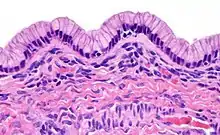

Histopathology

In case an ovarian cyst is surgically removed, a more definite diagnosis can be made by histopathology:

| Type | Subtype | Typical microscopy findings | Image |

| Mucinous cystadenoma | Lined by a mucinous epithelium |  | |